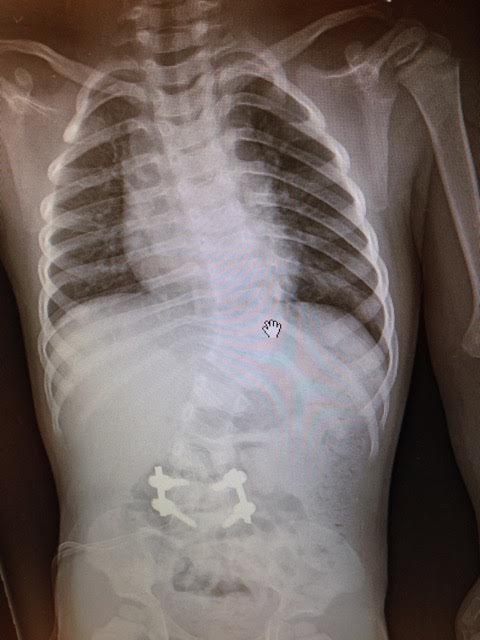

My husband and I noticed Carson’s spine appeared to be curved when he was just 5 months old. I brought up our concerns to his pediatrician at his 6 month appointment. She dismissed our concerns, saying babies are just flexible and they don’t have very strong muscles to hold themselves properly. When Carson was 10 months, he was having testing done for another medical condition. During that test my husband asked the radiologist to shoot a film of his spine because we were so certain he had scoliosis….and there it was…a very obvious “s” shaped curve, 60 degrees thoracic and 45 degree lumber. With that we started our research.

We started with a local orthopedic doc where we lived. We knew that this wouldn’t be the doc to manage him long term, but we wanted to get things started. He did an x-ray and told us Carson had a congenital defect, a hemivertebrae between L4-L5. A couple weeks later Carson had an MRI and CT done under general anesthesia. We looked for docs that were treating a lot of infants with congenital scoliosis. We found that many claimed to specialize in pediatric scoliosis but we wanted a doc that was treating infants and toddlers, not just teenagers.

He wore that brace until September 24, 2013, his surgery day, just 1 month after turning 2. The plan was to remove the hemivertebrae and fuse L4 and L5. The total OR time was to be about 3 hours. Everything went smoothly with his surgery. His curves decrease to 48 degrees thoracic and 38 degrees lumbar. We saw him in PACU at about noon that day. He was screaming and in a lot of pain. The next 48 hours where the worst days I have ever experienced.